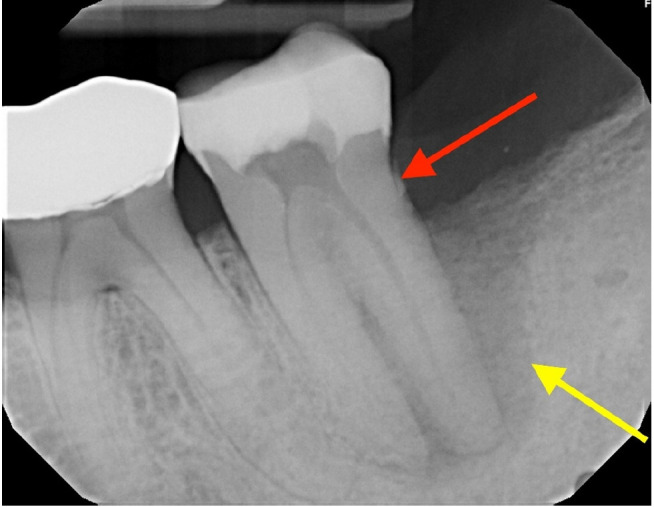

牙髓-牙周病变并发牙髓撕裂是一个诊断和治疗上的挑战。本病例报告描述了一位66岁男性下颌第二磨牙患者(#18)的成功治疗,该患者表现为EPL合并骨水泥撕裂。临床检查显示窦道引流,牙周深袋,x线表现为“j形”病变和不透射线的骨水泥碎片。该牙齿曾接受过牙髓治疗。多学科的方法包括牙髓治疗和手术切除骨水泥撕裂。在24个月的随访中,临床和影像学检查显示牙周健康、骨再生和病变消退有显著改善。本病例强调了在鉴别诊断epl时考虑骨水泥撕裂的重要性,并证明了牙髓-牙周联合入路对实现可预测结果的有效性。

Endodontic-periodontal lesions (EPLs) complicated by cemental tears present a diagnostic and therapeutic challenge. This case report describes the successful management of a 66-year-old male patient with a mandibular second molar (#18) exhibiting an EPL complicated by a cemental tear. Clinical examination revealed a draining sinus tract, deep periodontal pockets, and radiographic evidence of a "J-shaped" lesion and a radiopaque cemental fragment. The tooth had previously initiated endodontic treatment. A multidisciplinary approach involving endodontic treatment and surgical removal of the cemental tear was implemented. At 24-month follow-up, clinical and radiographic examination revealed significant improvement in periodontal health, bone regeneration, and resolution of the lesion. This case highlights the importance of considering cemental tears in the differential diagnosis of EPLs and demonstrates the efficacy of a combined endodontic-periodontal approach for achieving predictable outcomes.